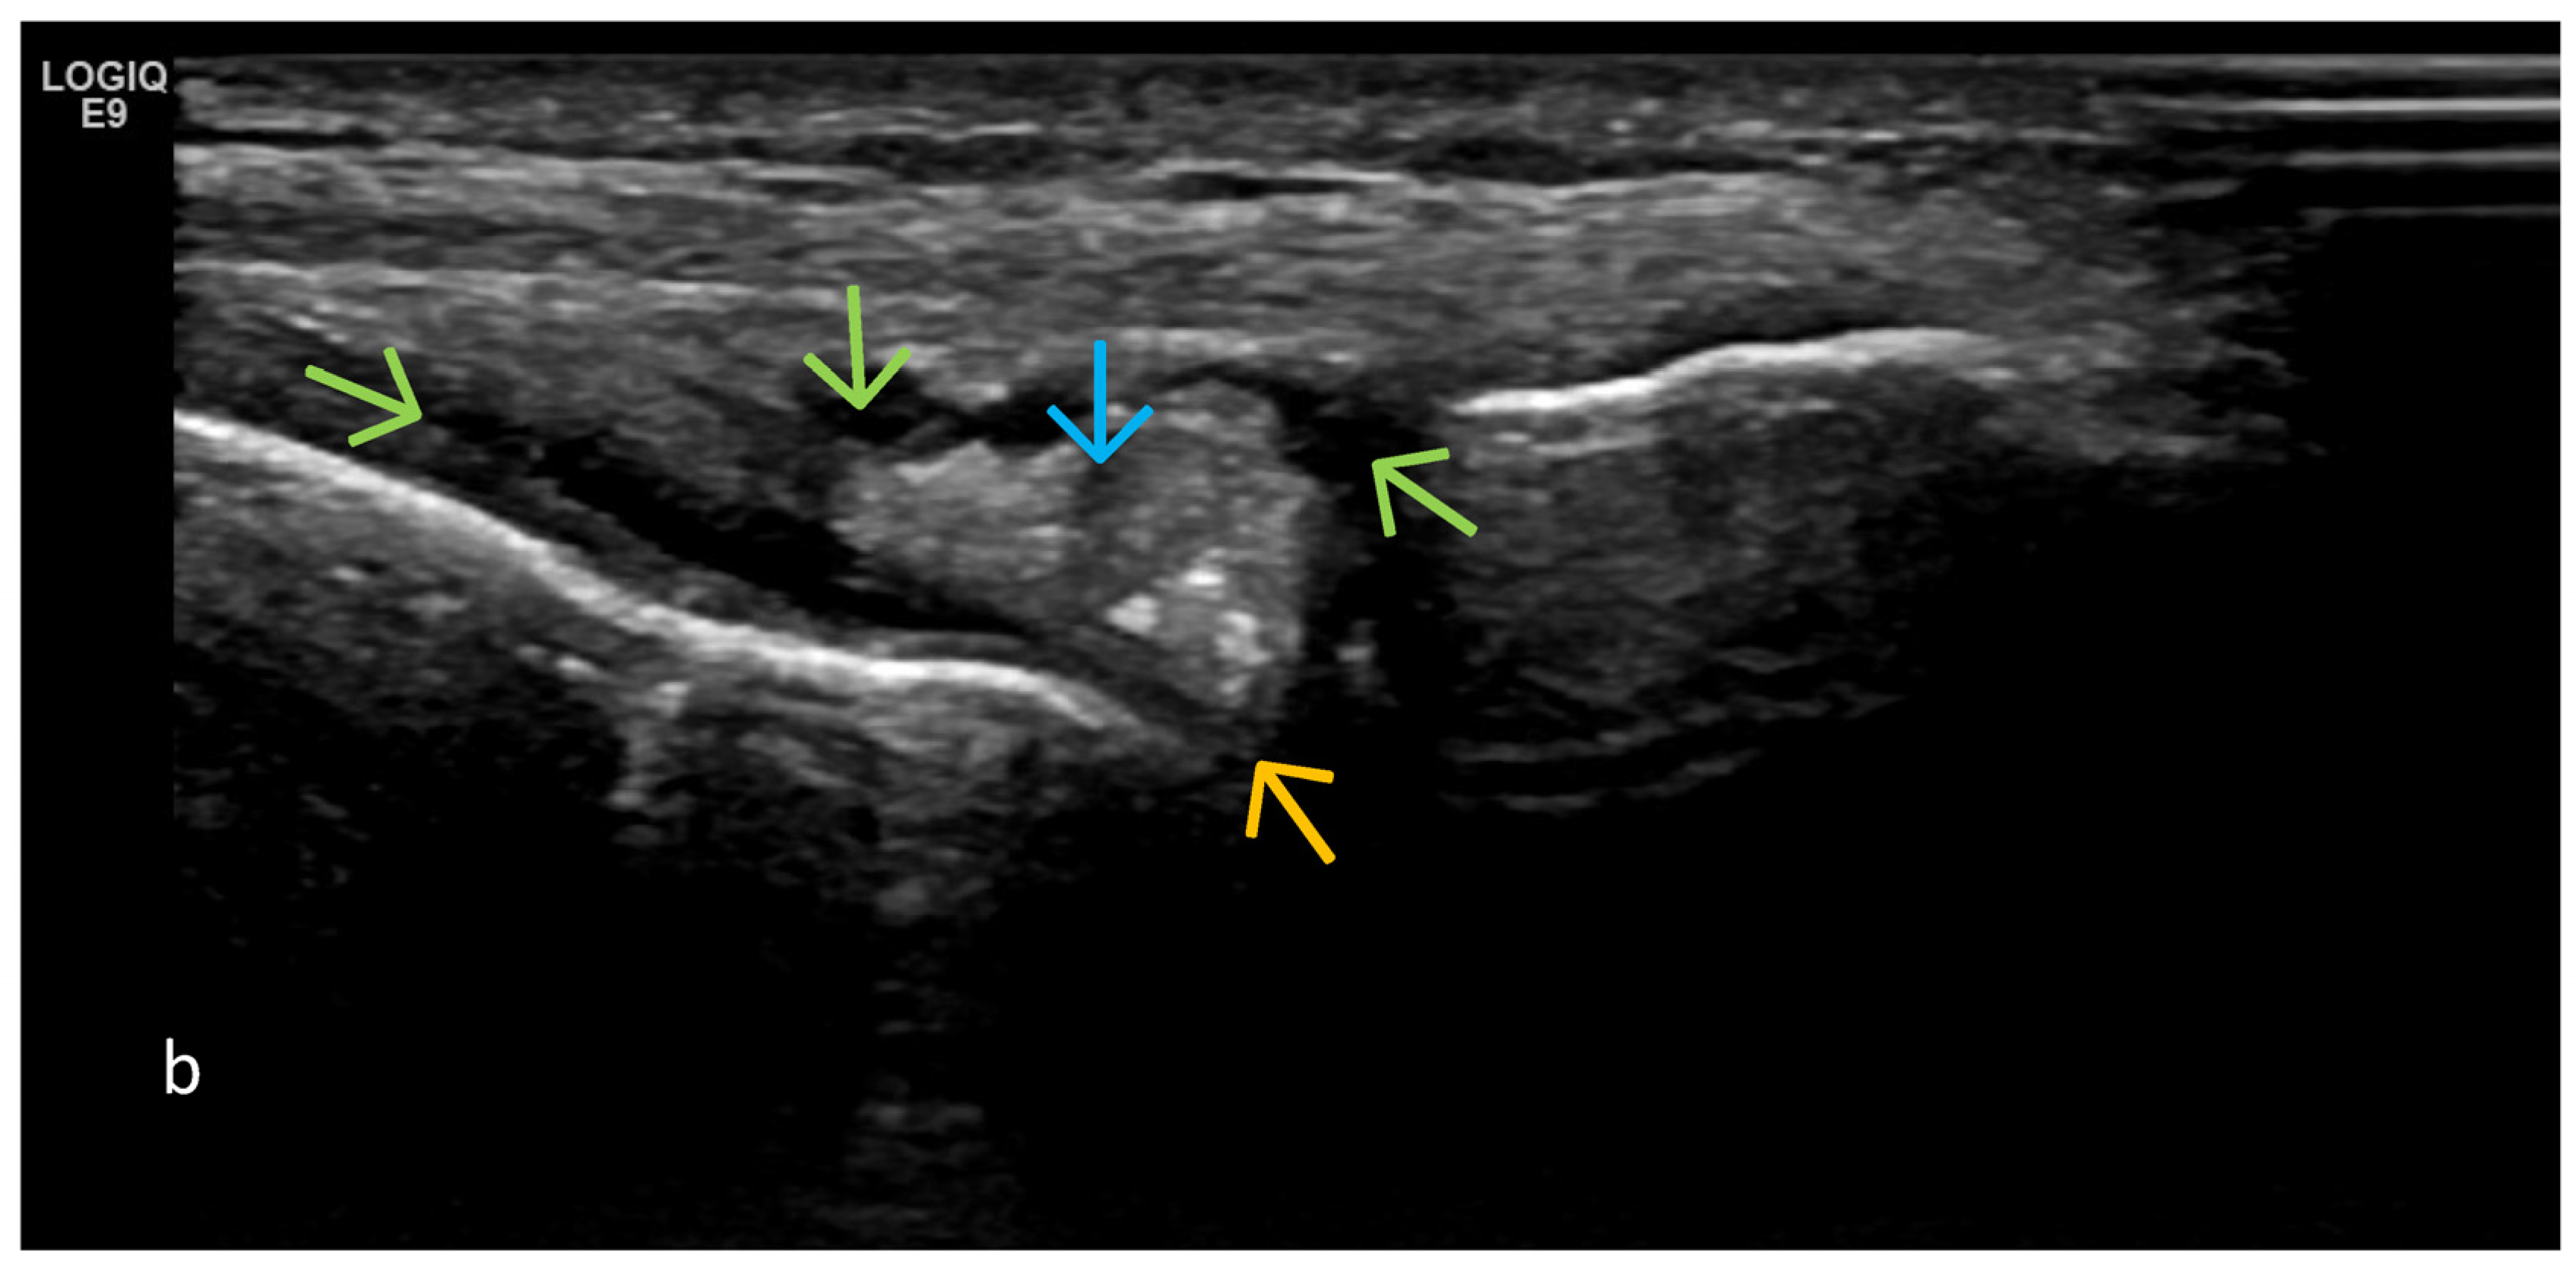

3. Suggestions for US Phenotypes

- Predominant intra-articular effusion (with minimal synovial proliferation (synovial sacs) and large intra-articular effusion;

- Predominant synovial proliferation, fat pads, and Hoffa synovitis (with a small amount of intra-articular effusion);

4. Examples of US Phenotypes